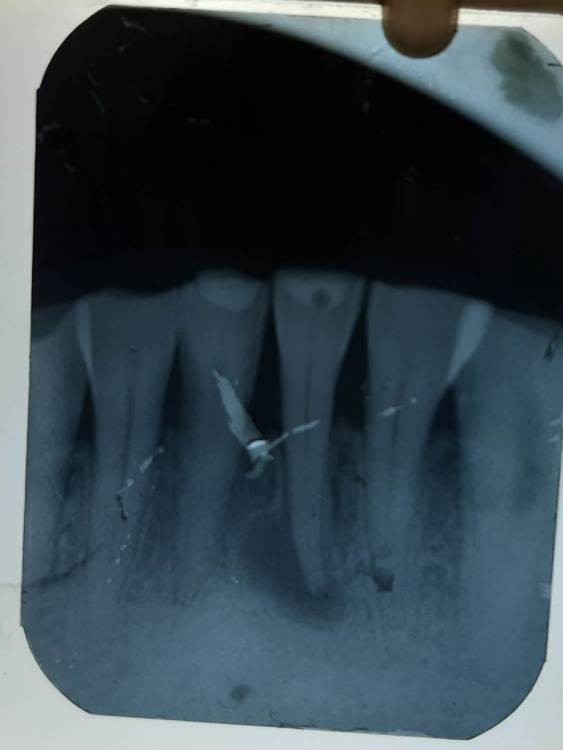

Lyubanya Опубликовано 17 апреля, 2022 Поделиться Опубликовано 17 апреля, 2022 Коллеги, помогите советом. Вчера принимала по скорой. 41 зуб, 2 канала. Перкуссия +, есть подвижность. Жалобы были на ноющую боль в том числе и ночью. При вскрытии получила кровянистый экссудат, обработка пока была только ручными до 25ого. Ирригация гипохлоритом, оставила кальций и закрыла. Сушила пинами в конце, были сухие и без крови в том числе. Обострилось, сегодня пациентка звонит что болит сильнее, отек, полночи дергало, темпа 37,8 и Нимесил не особо берет. Открывать его обратно? Может я кальций умудрилась за верхушку вывести? Как помочь? Ссылка на комментарий

1586Doc Опубликовано 22 апреля, 2022 Поделиться Опубликовано 22 апреля, 2022 (изменено) почитал коллег, я наоборот раскрываю и мою до 30.06 а то и 35.06 ( когда плохо раскрываем канал - получаем плохую обработку, плохо отмываем ирригацией, больше шанс вывести хлорку за апекс или вывести за апекс кальций. Далее ирригация с уз обязательно. сушка и кальций. Если на следующий день есть отек, к хирургу на разрез и антибактериальную терапию. Кальций меняю несколько раз, пока он не будет кристально белый при удалении временной пломбы. На Вашем снимке похоже стираемость у пациента, возможно отсутствие жевательной группы зубов. Я бы учел это и подвижность зубов. Изменено 22 апреля, 2022 пользователем 1586Doc Ссылка на комментарий

Гарриевич Опубликовано 22 апреля, 2022 Поделиться Опубликовано 22 апреля, 2022 (изменено) Изменено 22 апреля, 2022 пользователем Гарриевич 1 1 Ссылка на комментарий

Гарриевич Опубликовано 22 апреля, 2022 Поделиться Опубликовано 22 апреля, 2022 7 минут назад, 1586Doc сказал: Док, тут вы 50 размер используете)) Кейс хороший Вы в ручную до 50 размера ? Но конус то 02:) нет, тут 50 ручной ради картинки вставлен, чтобы сбить докторов с толку. Из ручных я использую только 10 и 15 Только что, Dent32 сказал: Канал, который закрыла кальцием. "По скорой" работал, там нет времени расширить до 40, промыть. На это нужно 5 минут, если нет 5ти минут зачем вообще брать пациента? 1 Ссылка на комментарий